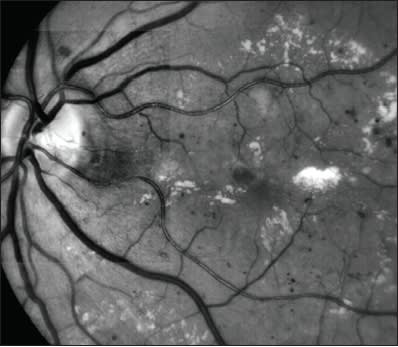

Figure 2. Branch retinal vein occlusion with macular edema and exudative foveal detachment: clinical photograph and OCT images.